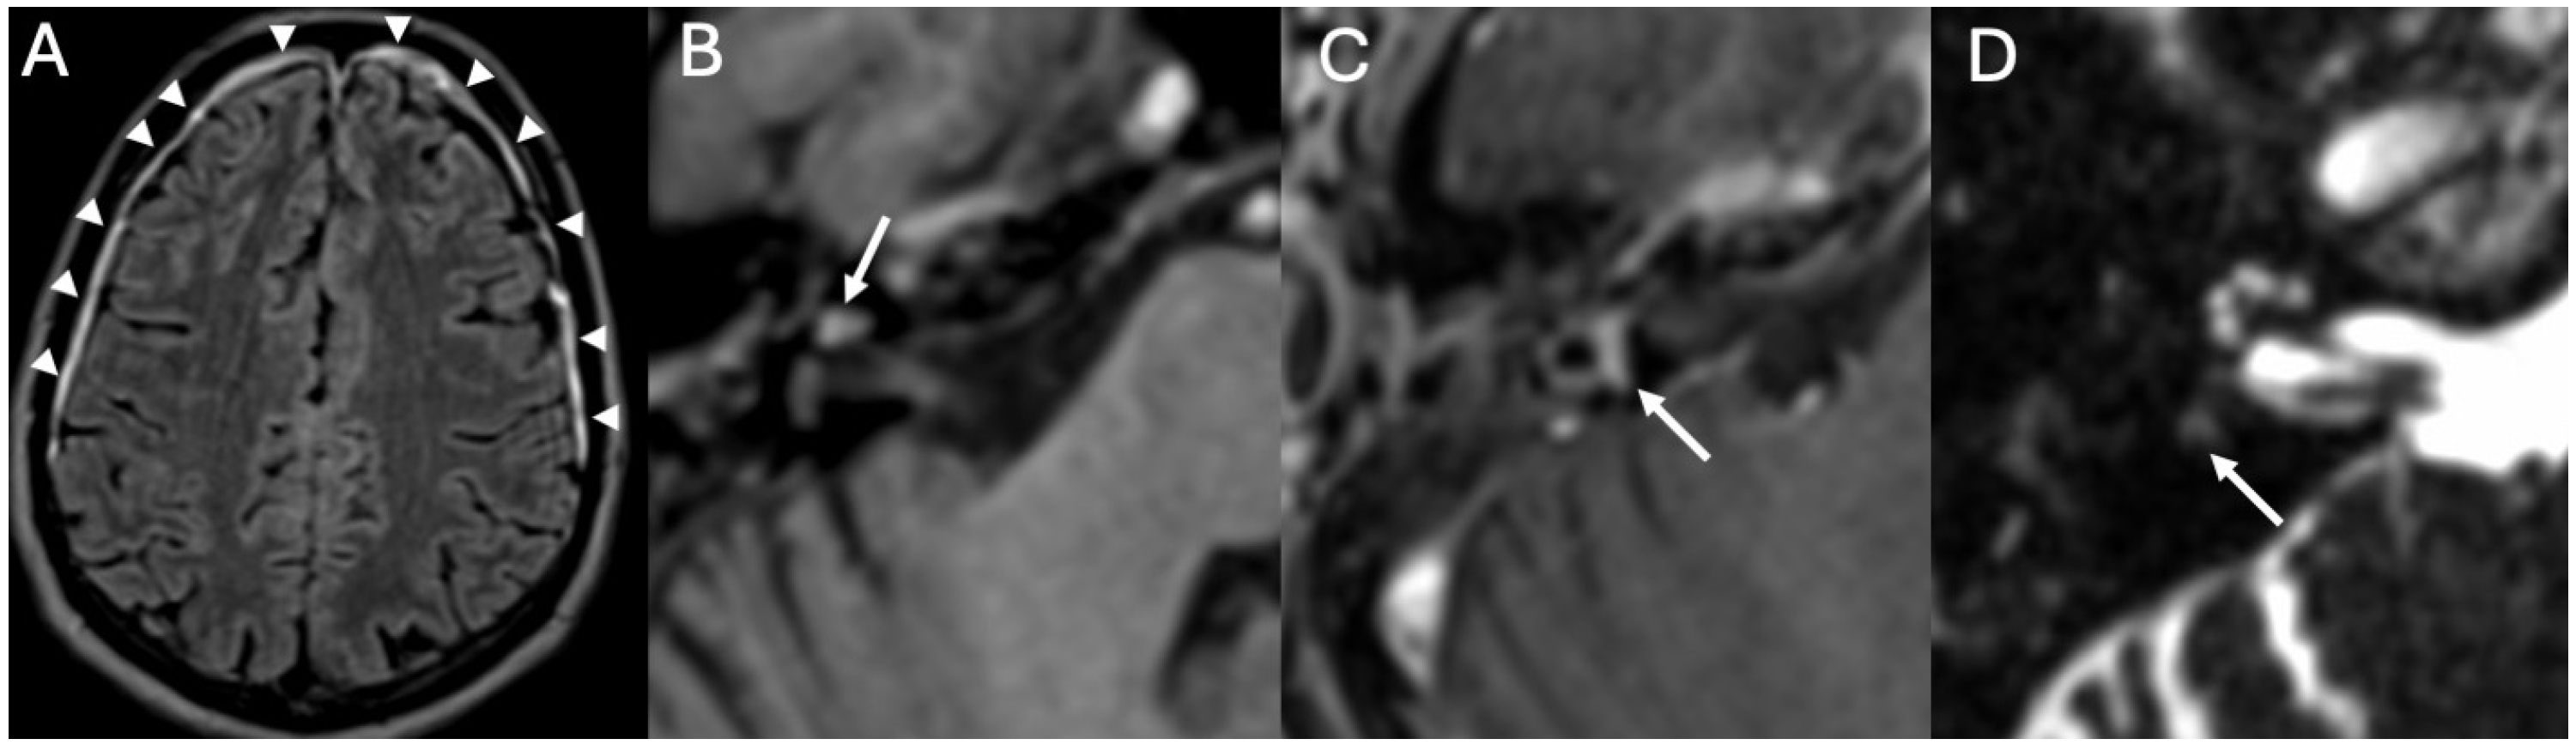

3.2. Bony Dehiscence

3.3. Cholesteatoma

| Bony Dehiscence/Temporal Bone Defects | Barbara et al., 2022 [22]; Sanna et al., 2009 [23]; Lim et al., 2012 [24]; Rabiei et al., 2025 [25] | Case-based studies and reviews | Tegmen tympani or semicircular canal defects create a route for meningitis and meningoencephalocele; HRCT coronal reconstructions preferred. |